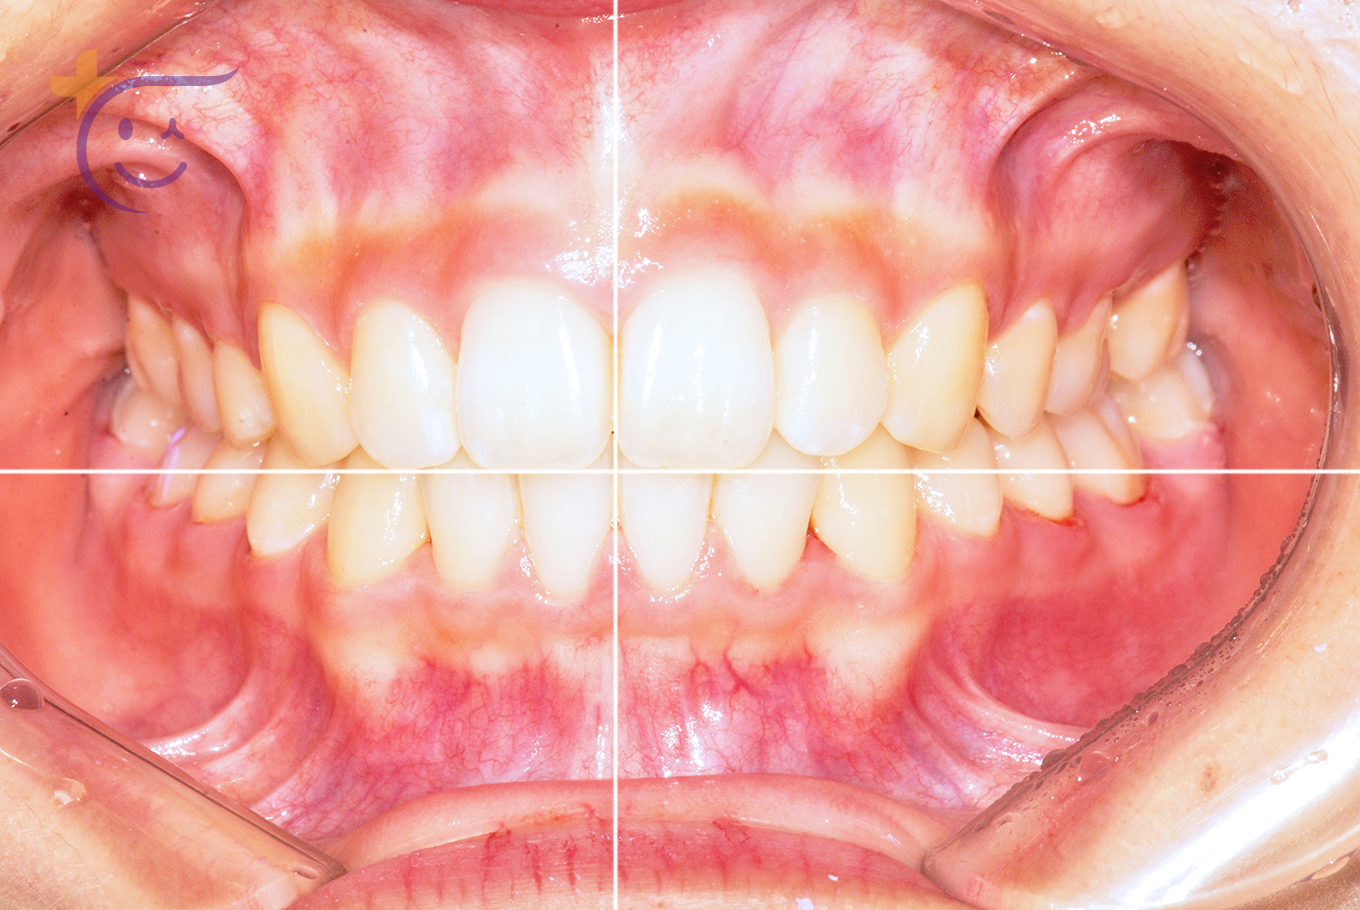

연세플러스 교정

교정, 단순한 치아 배열이 아닙니다.

과학과 경험, 그리고 심미적 안목으로 얼굴의 균형과 조화를 완성합니다.

수술 없이도 균형있고 아름다운 변화를, 연세플러스 치과가 약속드립니다.